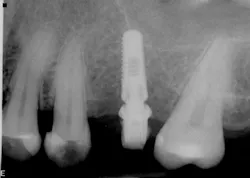

The most critical aspect of any implant system is the interface between the implant fixture and its surrounding bone (figures 1-5). Integration between the fixture and its surrounding bone is the foundation of modern implant dentistry. There is little we can do to modulate bone healing, but we can modify the implant fixture itself.

Figures 1-5: Figures 1 through 4 illustrate, respectively, a seven-year follow-up visit and a three-year follow-up visit of two different implant systems. Implant No. 22 (figure 5) shows peri-implant radiolucency following functional loading, indicating fibroencapsulation and loss of integration into bone, necessitating removal.